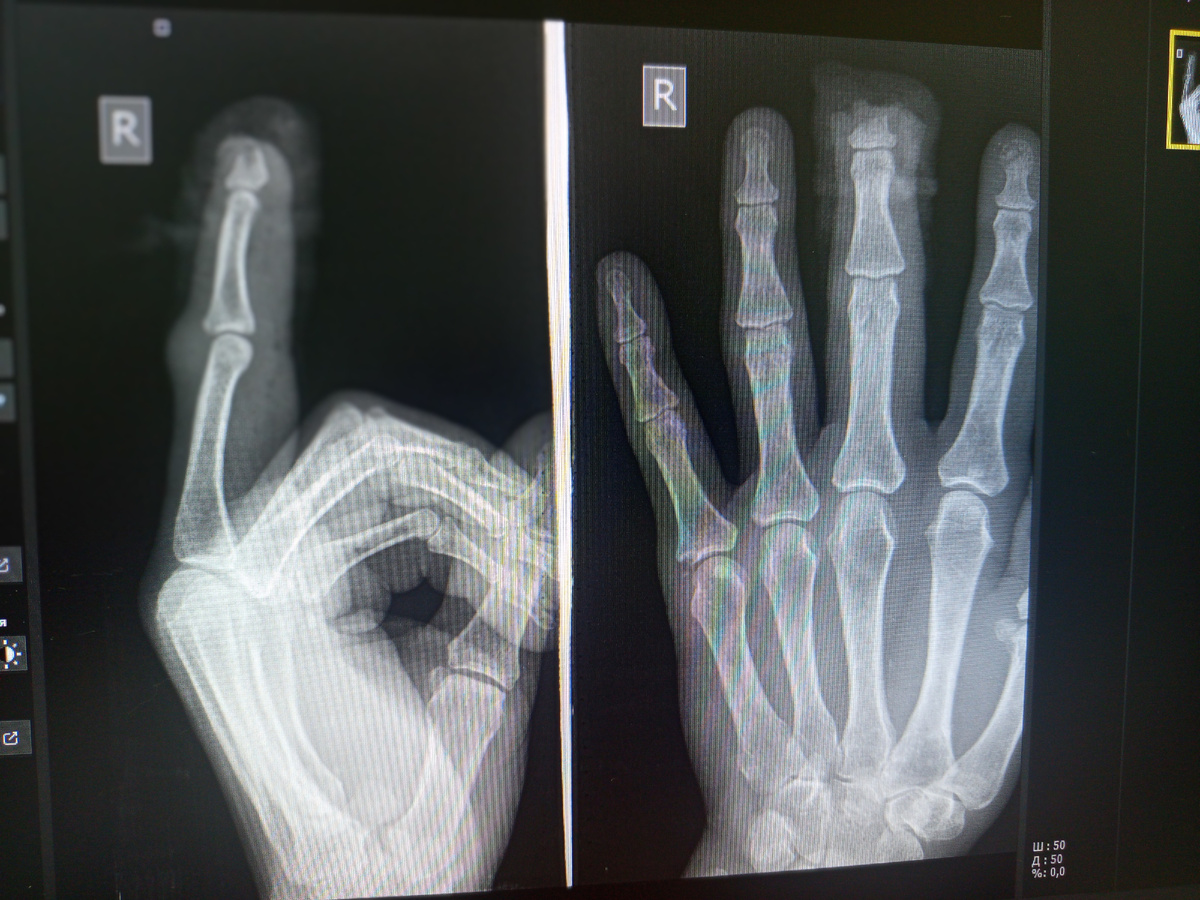

–Так , ага, –смотрит он снимок. –Хотел поровнее сделать , а ладно , так сойдет!

Мозоль какая хорошая наросла за полгода!

–А винты -то оба сломаны у вас.

–Оба , да? Ну травматолог так и сказал , что надо снимок сделать.

–Нет , на второй прямой все видно , что винты целые.